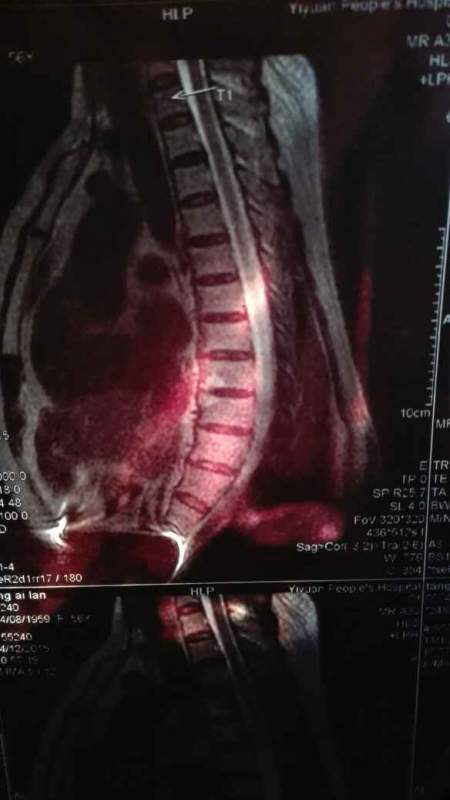

用手机拍的核磁共振和检查报告单

妈妈胸椎终板炎

前辈,这是12.14做的MR影像。